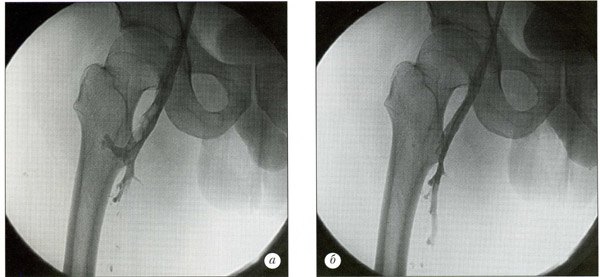

Диагностика острого венозного тромбоза в амбулаторных и в стационарных условиях базируется на оценке клинической симптоматики и результатах инструментальных методов обследования и должна осуществляться в кратчайшие сроки поскольку от быстроты определения самого факта тромбоза, его локализации, характера проксимальной части тромба зависит клинический прогноз. Во всех случаях острого венозного тромбоза обследование предпочтительно начинать с ультразвукового ангиосканирования и лишь тогда, когда визуализация затруднена (например, подвздошно-кавального сегмента) или в тех случаях, когда при наличии клиники илиофеморального флеботромбоза осуществить верификацию диагноза неинвазивно невозможно показано выполнение в экстренном порядке рентгеноконтрастного исследования. Скрининговым методом диагностики острого венозного тромбоза стал на сегодняшний день тест на Д-димер. Отрицательный его результат исключает венозный тромбоз с вероятностью 95-98% у пациентов с низким риском его возникновения.